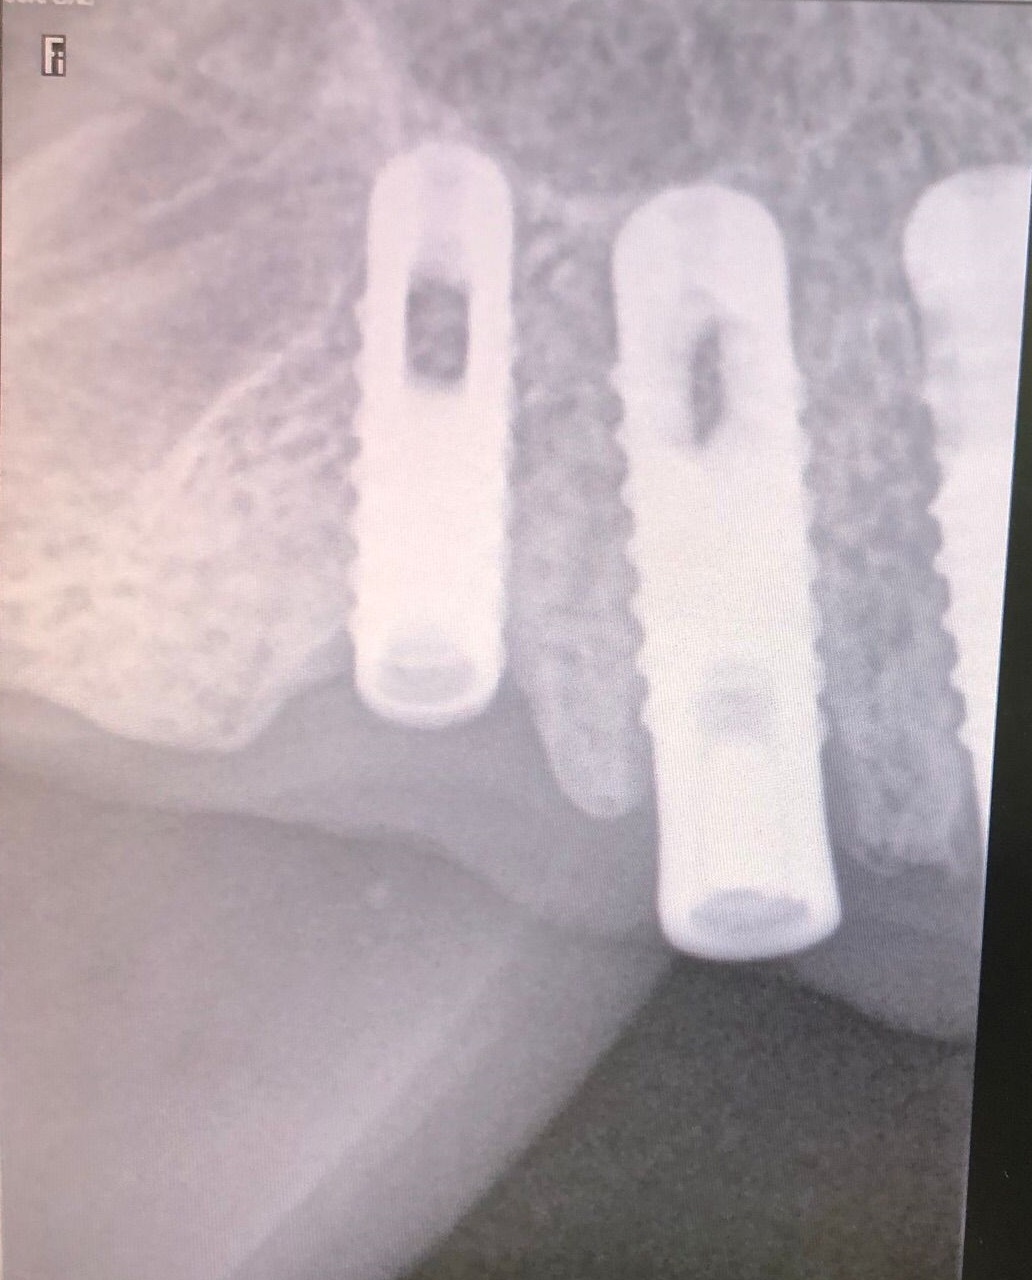

Actualmente vuelve el paciente de nuevo con la misma prótesis. Había roto dos de los tres pilares en concreto los más distales. El primero de los dos había roto la rosca del aditamento dentro del implante como ocurre habitualmente. Pero el ultimo pilar había roto directamente la cabeza del implante tal como se ve en la radiografía y lo que quedaba era un cilindro de titanio macizo perfectamente integrado en el maxilar, sin posibilidad de enroscar nada. Le explicamos al paciente que habría que quitar y poner un implante en el mismo acto. El paciente dijo que no, así que decimos que no se haría cirugía. Buscamos solución alternativa: hacemos un un agujero en el centro del macizo cilíndrico del implante roto y pasamos sucesivamente el set de machos roscantes. Utilizamos una fresa cañón de 1 mm que poco a poco se va introduciendo hasta 8mm con un poco de vagación, que hace que sea un poco mas de 1mm de diámetro. Posteriormente pasamos el conjunto de machos roscantes de métrica 2mm para poder usar un aditamento experimental, que era un palo de rosca de diámetro 2 mm unido a un cuerpo metálico en forma de sombrero napoleónico fabricado en cromo/cobalto, prototipos primitivos de la sistemática ASATIM y que tienen la característica de tener gran resistencia a la fractura. Nos llevó un tiempo largo el tallado de dichos aditamentos, tal como se puede observar en las imágenes, y tras cicatrizar la encía se le hizo una prótesis estándar. Esperemos que no lo rompa más veces.